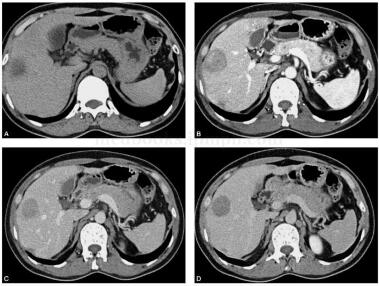

患者,女性,40岁,主诉:体检发现肝脏占位1周。病来患者无发热,无腹痛、腹胀,无血及黑便,体重未见下降。既往否认肝炎、结核病史。有长期口服避孕药史。查体:皮肤及巩膜无黄染,腹软,无压痛,无反跳痛及肌紧张,未触及局部包块,肝脾肋下未及,墨菲征(-),肝区叩痛(-),移动性浊音(-)。AFP:12ng/ml。CT增强检查如图2。

图2 CT增强扫描:考虑肝细胞腺瘤。CT平扫显示肝S5段稍低密度灶,边界模糊,增强扫描后动脉期呈结节样强化,门脉及静脉期结节强化减弱,低于周围肝实质